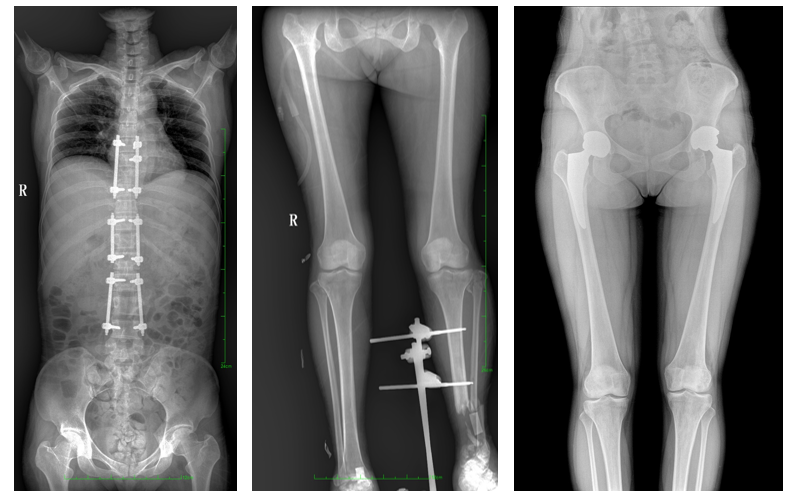

普爱医疗自主研发的一款数字化X光机——PLX8600大视野平板动态DR,拥有43cm*86cm超大有效视野,可一次性拍摄全脊柱、双下肢的影像视野。使全脊柱及双下肢能够得到完整清晰的成像,为临床在脊柱侧弯畸形和下肢骨关节病变诊断、治疗方案制定及治疗后复查提供精准的测量。